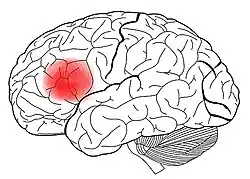

Die Broca-Aphasie ist eine nach dem französischen Anatom und Chirurgen Paul Broca benannte Aphasie (Sprachstörung), bei der hauptsächlich die Sprachproduktion beeinträchtigt ist.

Gewöhnlich finden sich bei einer Broca-Aphasie ausgedehnte Schäden des frontalen Kortex.[1]